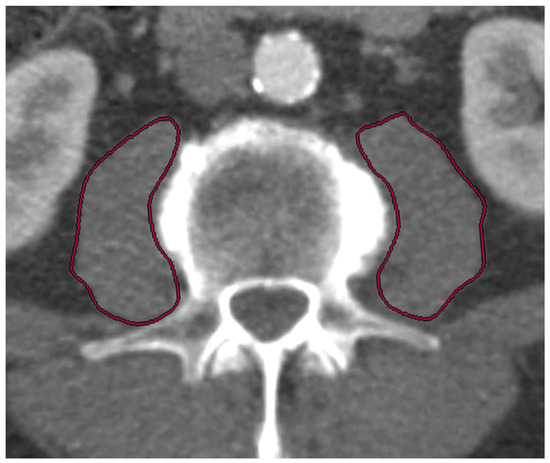

2.3. CTA Protocol and Measurement of PMAi for Sarcopenia Assessment